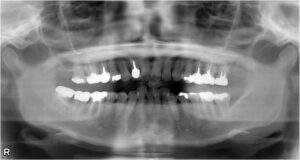

上下臼歯9本欠損症例

BEFORE AFTER 74歳女性/上下9本欠損/インプラント埋込手術 【治療内容】 根っこの先で炎症が広がり抜歯とな…